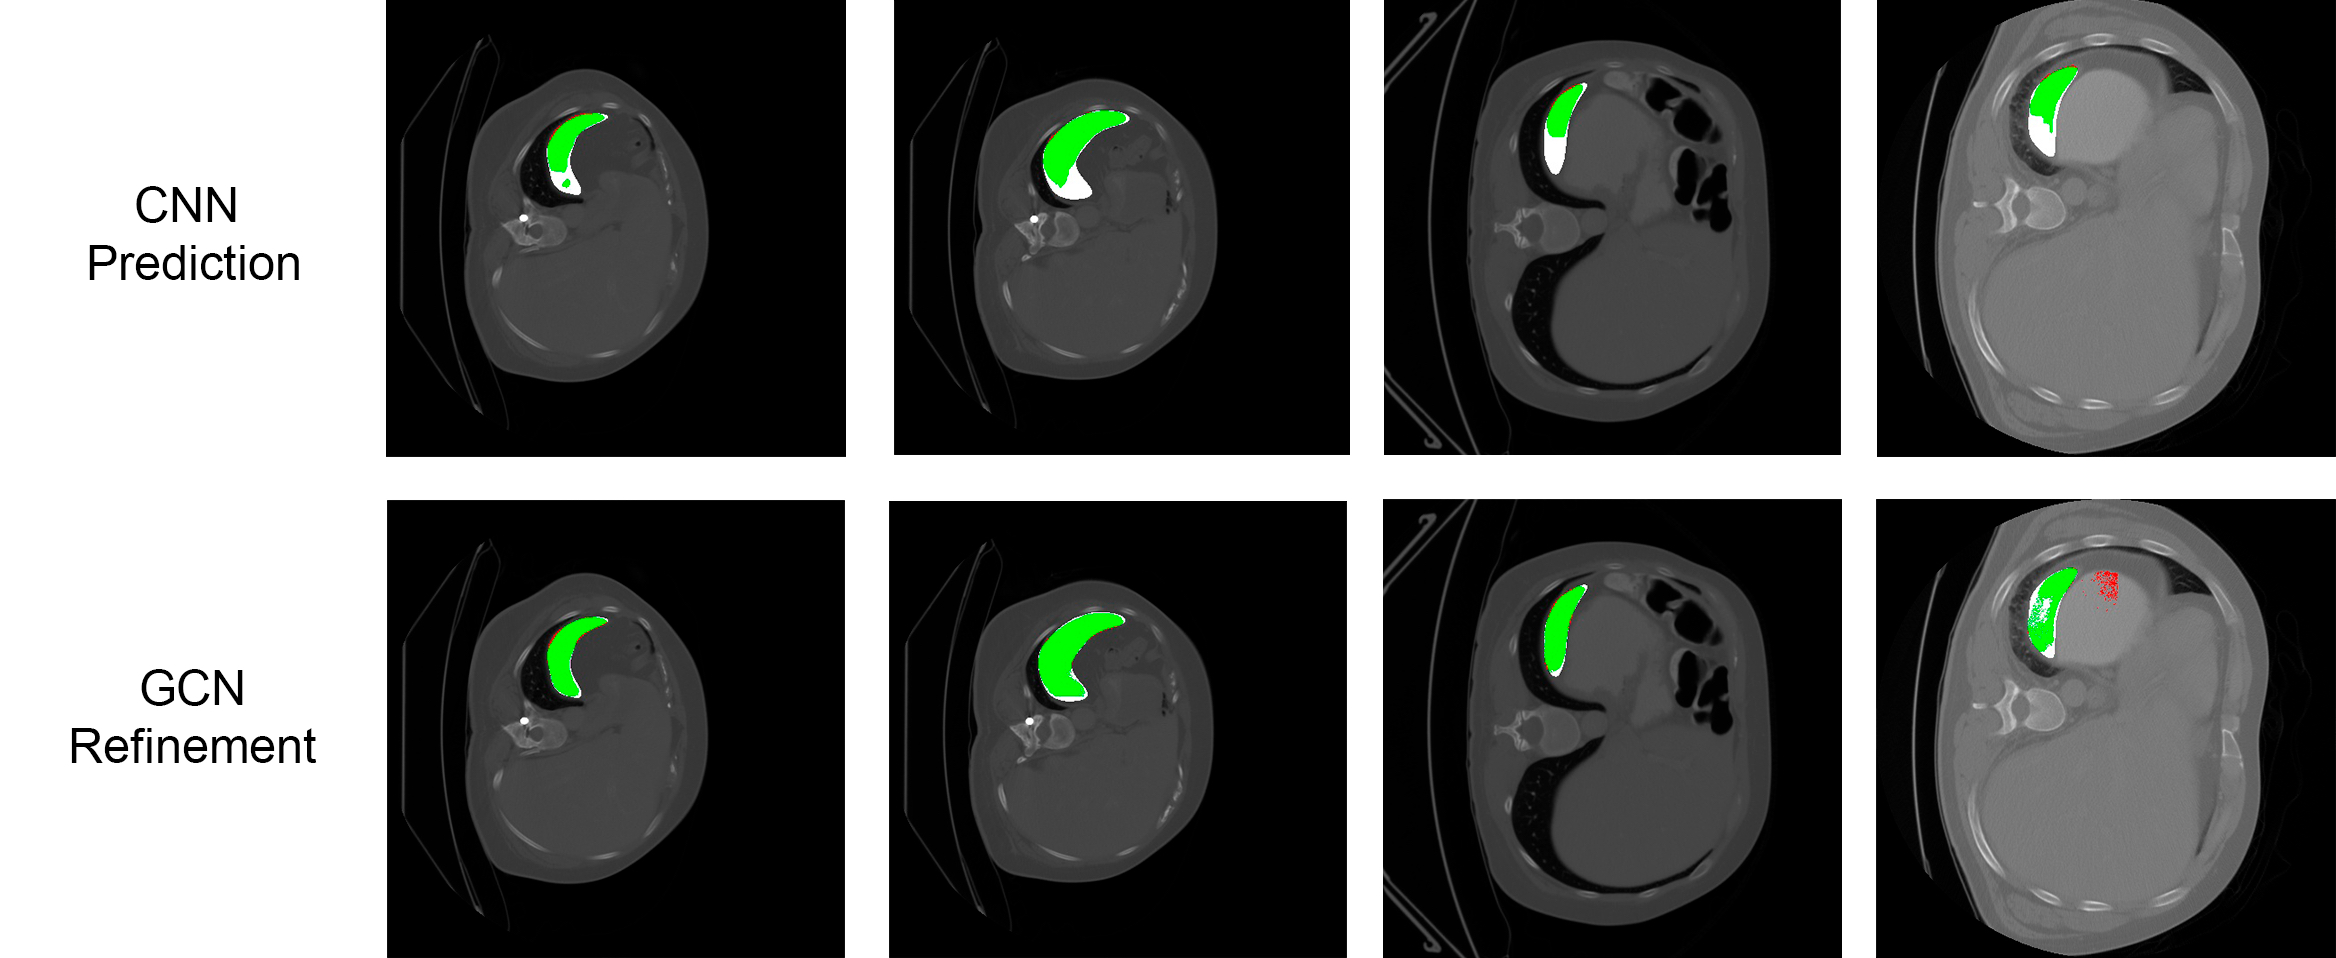

Results are presented in Table 1. The GCN-based refinement outperforms the base CNN model and the CRF refinement by around 1% and 0.6% respectively in the pancreas segmentation task. For spleen segmentation, our GCN refinement presented an increase in the dice score of 2% with respect to the base CNN, and 1.7% with respect to the CRF refinement. Figs. 2 and 3 show visual examples of the GCN refinement compared with the base CNN prediction.

Refer to caption

Figure 3: Comparison of the CNN prediction and its corresponding GCN refinement for spleen segmentation. Green colors indicate true positives (TP), red indicates false positives (FP), and white false negative (FN) regions. From left to right: the first, second and third columns show FN regions recovered. The fourth column shows an FN region recovered but also a new FP region generated.